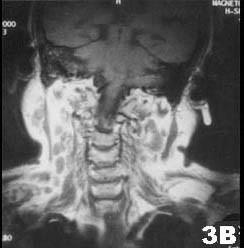

肺结核患者发现双侧腮腺区肿块3个月,缓慢增大,无明显症状。查体腮腺区可触及局限性肿块,边界清,质软,可活动,轻压痛。CT?检查结果图示。首先考虑的诊断为(...

问题 肺结核患者发现双侧腮腺区肿块3个月,缓慢增大,无明显症状。查体腮腺区可触及局限性肿块,边界清,质软,可活动,轻压痛。CT?检查结果图示。首先考虑的诊断为()

选项 A.腮腺囊肿 B.腮腺多形性腺瘤 C.腮腺结核 D.慢性腮腺炎 E.腮腺腺样囊性癌

答案 C